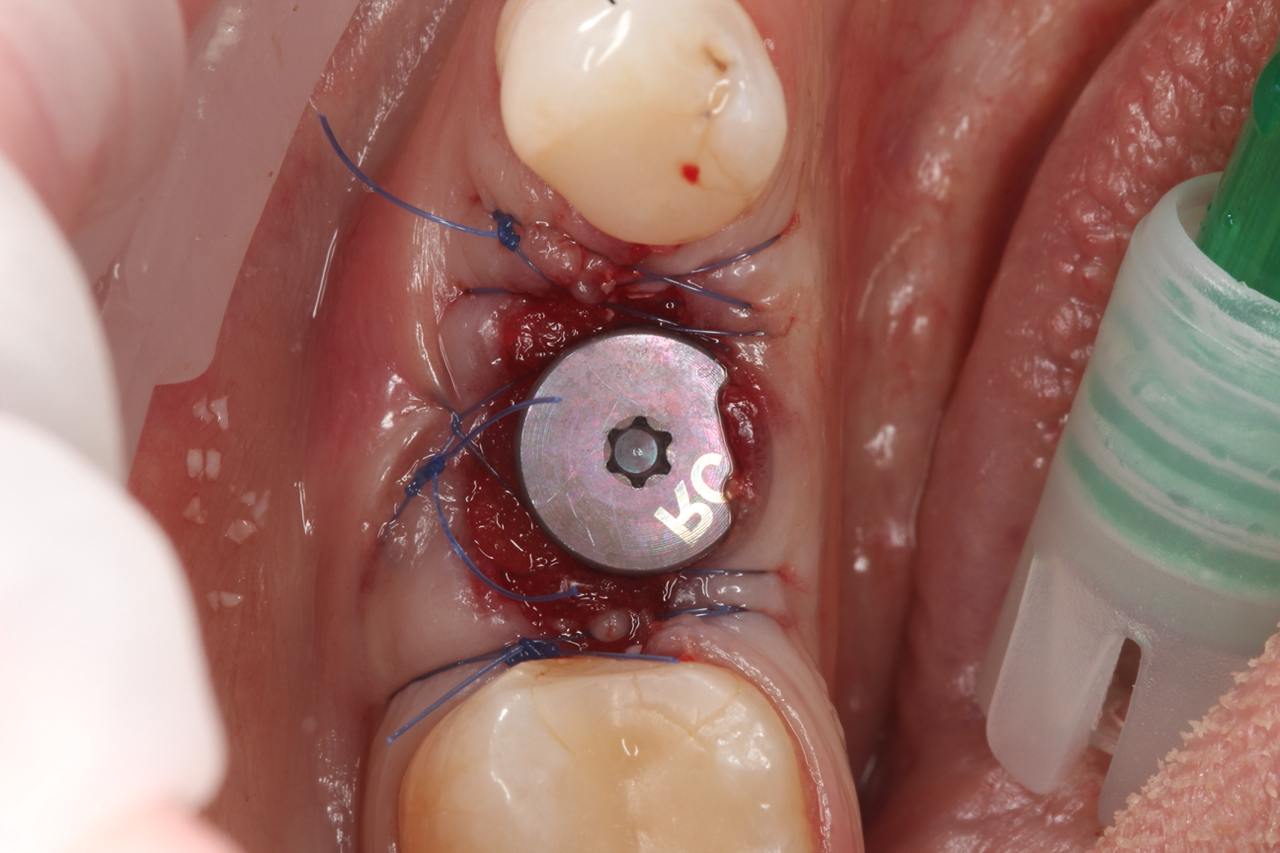

- аугментация лунки ксеногенным костным материалом Bio-Oss

- установка имплантата Straumann BLT 4,8 × 8 мм